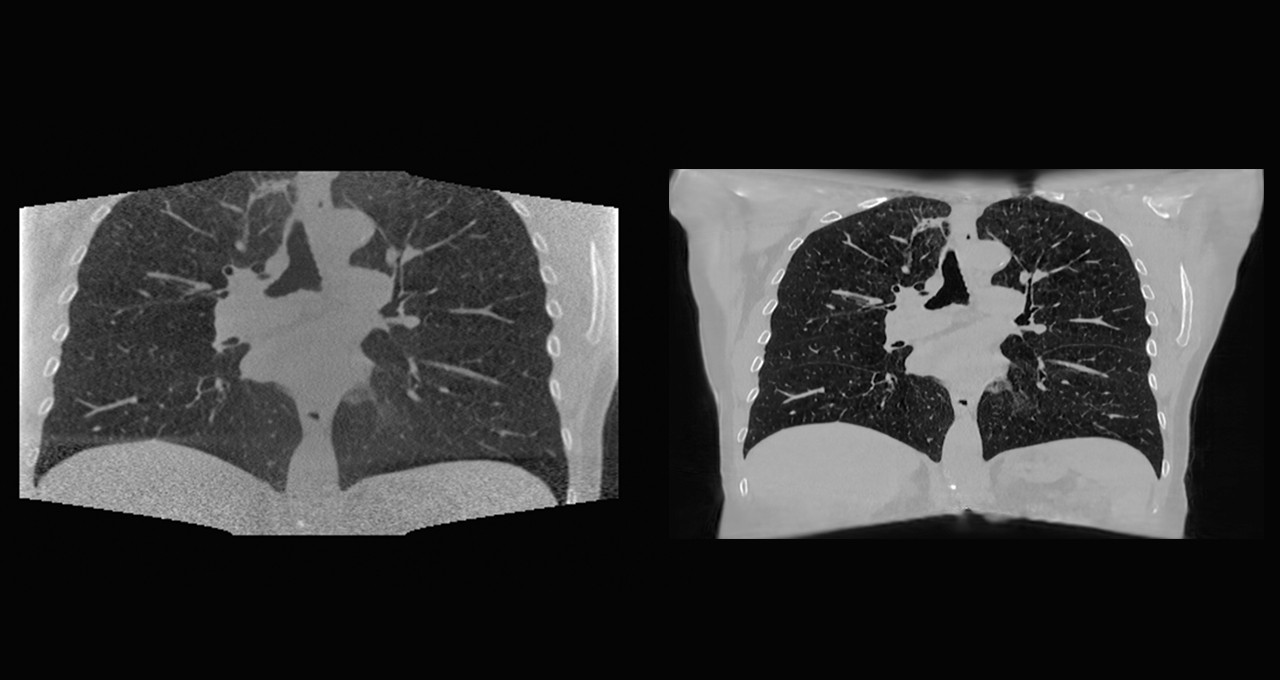

图注:NKI使用AI模型更好地重建锥形束计算机断层扫描(CBCT)胸腔图像,与传统方法相比,图像质量更清晰。

以前,NKI在较低分辨率的图像上对AI模型进行训练。现在,由于NVIDIA AI Enterprise提供了更高的内存容量,研究人员可以改为使用高分辨率图像进行训练。这种改进可帮助临床医生在患者每次接受治疗时更好地确定肿瘤的大小和位置。

NKI的研究人员将海量2D和3D数据源与AI相结合,使用NVIDIA AI Enterprise构建深度学习模型,在每次放疗前精准定位肿瘤位置。

“医生可以在治疗当天使用这种解决方案替代CT扫描,来优化治疗方案,验证放疗计划,”荷兰癌症研究所负责人Jonas Teuwen介绍说。

借助NVIDIA AI Enterprise,Teuwen在阿姆斯特丹的团队可以在硅谷托管的服务器上运行NVIDIA A100 80GB GPU上的工作负载。他们用了不到三个月的时间就成功建立了卷积神经网络,在对不到300个临床肺部CT扫描进行训练后,重构并推广头颈部数据。